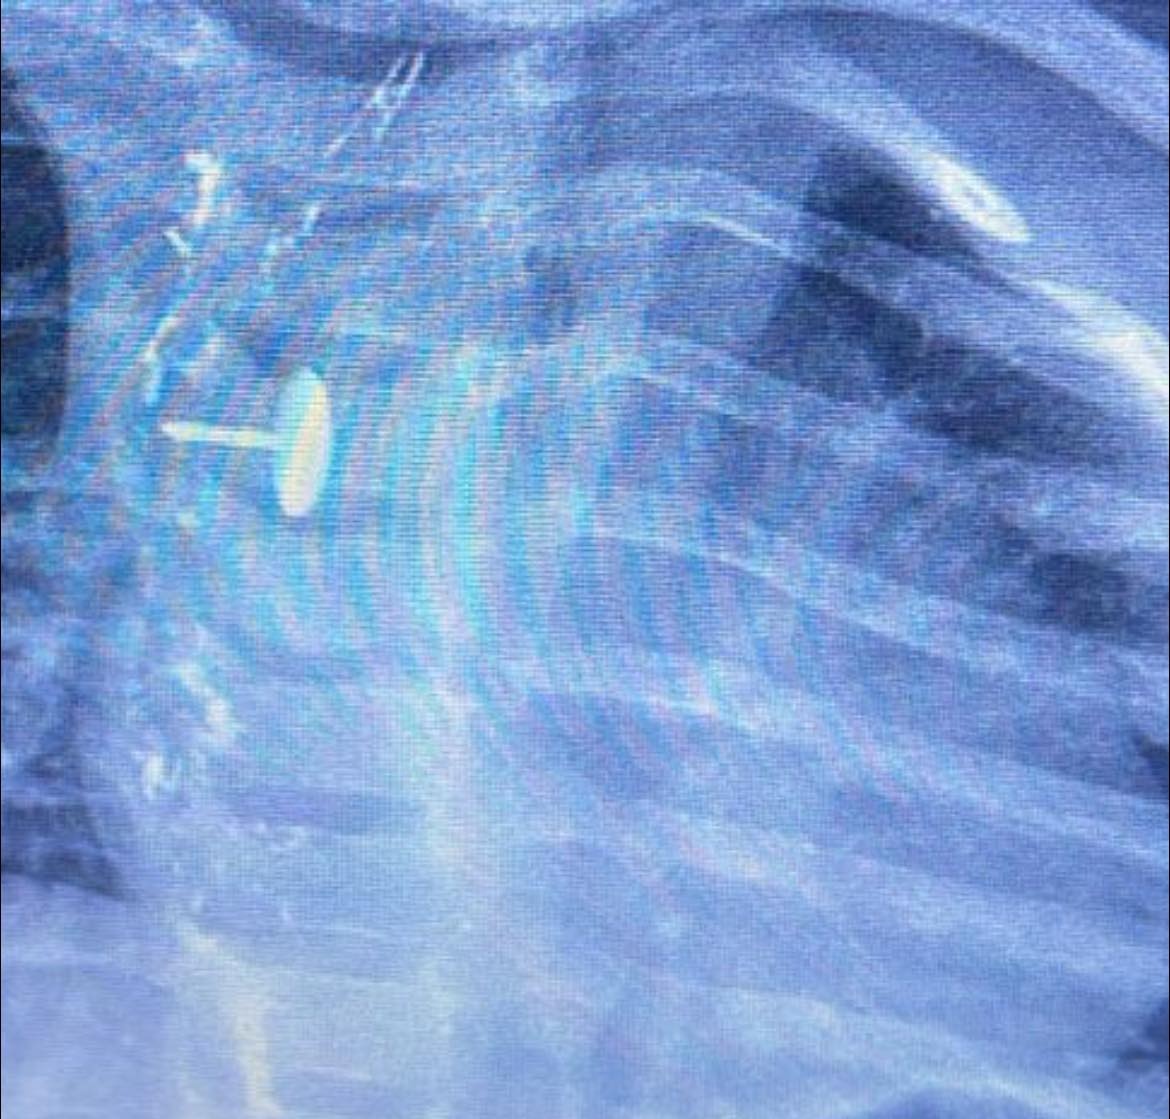

نجح فريق قسم جراحة الأطفال، بمستشفى الأطفال التخصصي ببنها، بمحافظة القليوبية، بقيادة الدكتور محمد متولي رئيس قسم جراحة الأطفال، في إجراء عملية دقيقة لاستخراج دبوس ضغط من مريء طفلة عمرها سنة و7 أشهر، كانت قد ابتلعته منذ 6 أشهر.

الجسم الغريب استقر داخل جدار المرئ

كشفت مستشفى الأطفال التخصصي ببنها، في بيان لها، أن الجسم الغريب استقر داخل جدار المريء، مما تسبب في عدم قدرة الطفلة على البلع طوال هذه الفترة، وجعل حياتها في خطر دائم.

دبوس ضغط فى مرئ طفلة